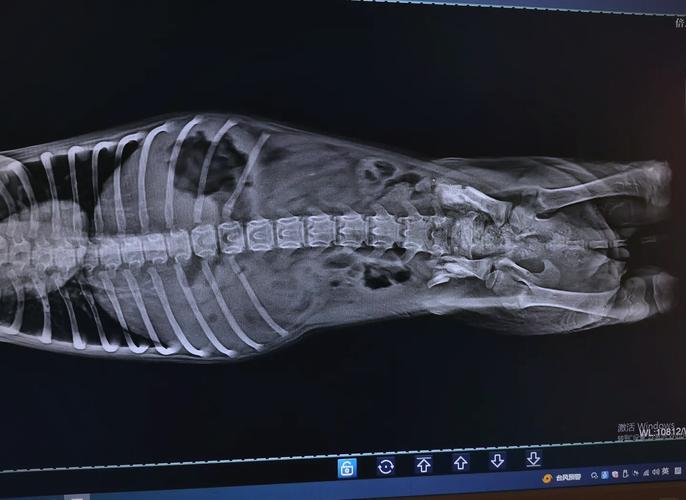

〖Three〗、及时送医:狗狗摔到腿后,为防止情况恶化,应尽快将其送至宠物医院。影像学检查:通过X光、CT等影像学检查,可以准确判断狗狗是否存在骨折以及骨折的类型和严重程度。X光是常用的检查手段,通常需要拍摄2张以上的X光片,以结合不同角度判断骨折情况。

〖Two〗、脱位程度分为四级,二级以上需手术治疗。髋关节发育不良多发于金毛、德牧等中大型犬,症状包括兔子跳行走姿势、起身困难,X光片可见股骨头变形。腰椎间盘突出在短腿犬种高发,病犬常因疼痛出现弓背、后肢颤抖,严重时导致瘫痪。